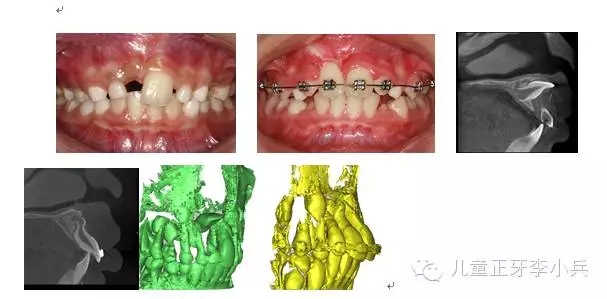

2. 彎根牙的早期牽引助萌:先天及乳牙外傷導(dǎo)致繼承恒牙牙冠及牙根發(fā)育異常,臨床出現(xiàn)牙冠發(fā)育不全及彎根牙。彎根牙的牽引助萌常受到彎根嚴(yán)重程度及彎根角度的影響,早期牽引能引導(dǎo)牙根形成方向,降低牙根彎曲的嚴(yán)重程度。(圖3,彎根牙的早期牽引治療)

41.webp.jpg

圖 3 11彎根牙的早期牽引,11牙根繼續(xù)發(fā)育,牙根彎曲程度減??;